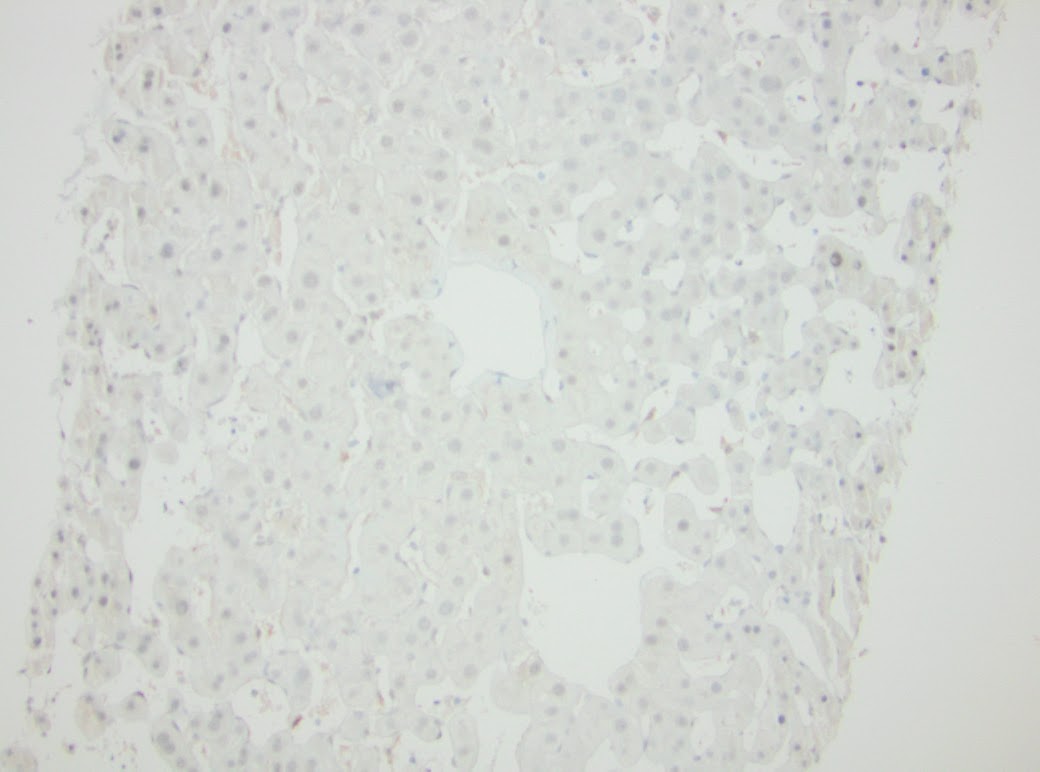

There is one vascular structure with fibrin within the lumen. No significant macrovesicular steatosis or inflammation is seen in either of the two liver biopsies. There are focal areas of hemorrhage and other areas with hepatocyte dropout. Another liver biopsy was obtained from the patient four months later in June of 2015. Again, striking zone 3 hepatocellular atrophy and sinusoidal dilatation was seen (Figure 2.) Fibrin was identified in several of the portal venules (Figure 3).

| Figure 2. June 2015 biopsy 100X |